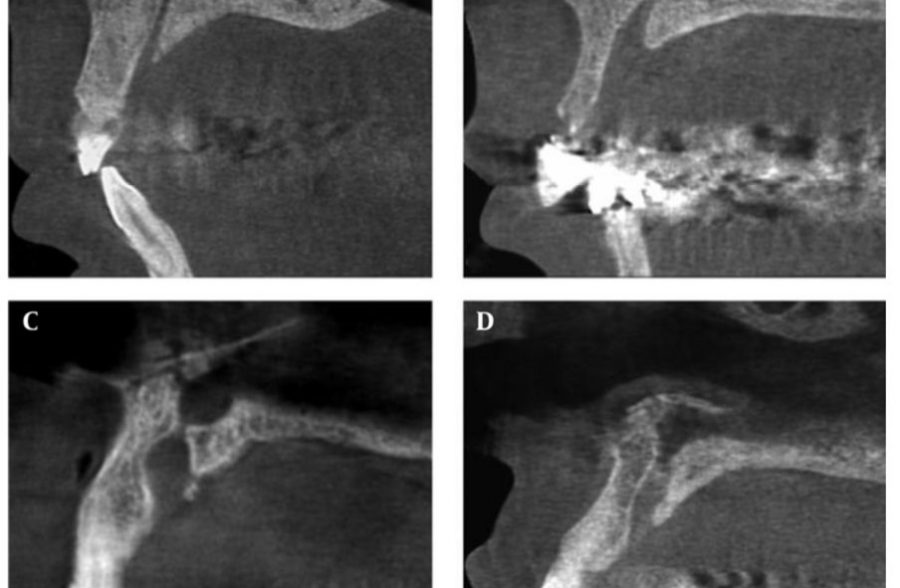

Assessment of Nasopalatine Canal Anatomic Variations Using Cone Beam Computed Tomography in a Group of Iranian Population